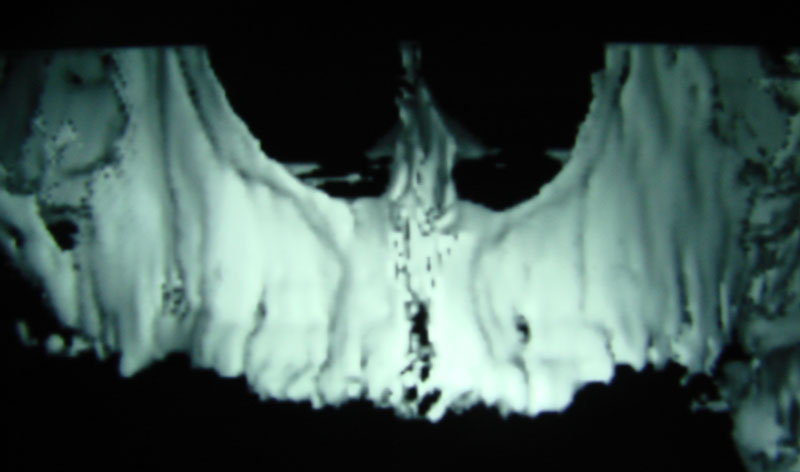

Existen muchas situaciones donde la pérdida y la atrofia ósea son tan graves que nos obligan a recurrir a la cresta iliaca del paciente, para conseguir el volumen óseo necesario para la correcta reconstrucción del maxilar. Así, la colocación de implantes será posible a los 3 meses.